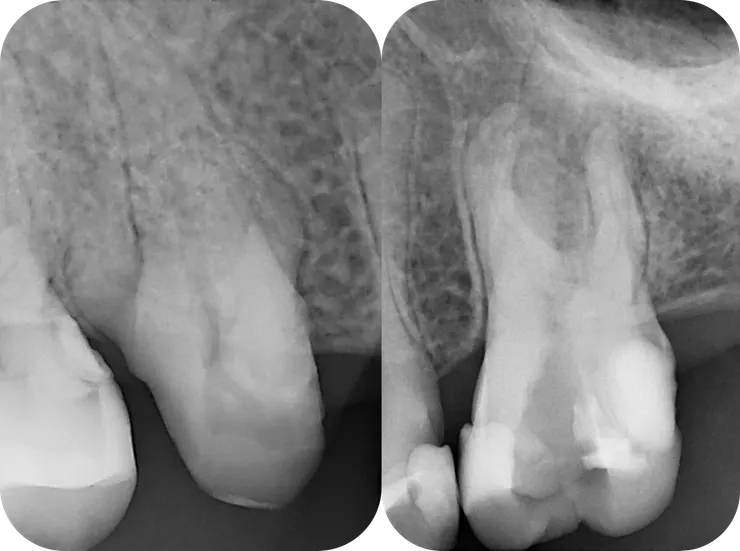

這篇的兩個主角分別是

左邊的 64 歲 16 (#20240611)

以及

右邊的 43 歲 26 (#20241224)

面對這種一看就知道絕非善類的 case, 最關鍵的步驟就是,在開始之前先仔細地把目標物清楚地描繪一番:

先如同橘色虛線般,將 root 的外型描繪出來 (相對單純的 palatal root 先忽略)。

然後再依據 root 的外型,將依稀可見的 canals 如同紅色線條般描繪出來。

腦中有了清晰的圖像後,才能以終為始的,一步步地完成後續的修形與封填。

(當然前提是必須有清晰的 initial PA, 而如果能藉由 CBCT 得到立體的架構那更好!)